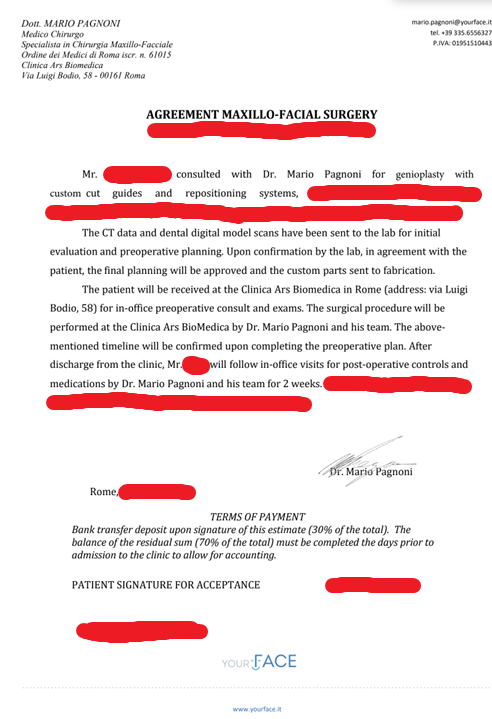

The Surgeon Question

I’m planning to visit Ramieri, Pagnoni, and Raffaini.

The Surgeon Question

I’m planning to visit Ramieri, Pagnoni, and Raffaini.

- Which of these do you think is the best and open to custom midface implants alongside the Bimax? (keeping in mind how much each surgeon charges)

- Should I do consultations with all three or is there a clear winner for this specific approach?